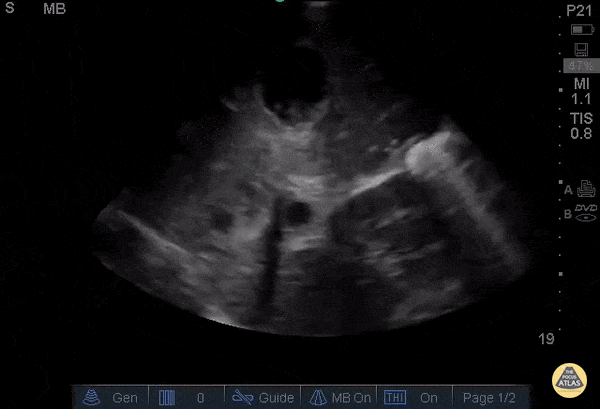

Incidental cystic and necrotic lesions seen throughout liver in a patient with hepatomegaly and abdominal pain on exam. Primary pancreatic CA (not shown). It is still difficult to have a poker face while finding surprise cancer with POCUS. Jason Tanguay, DO